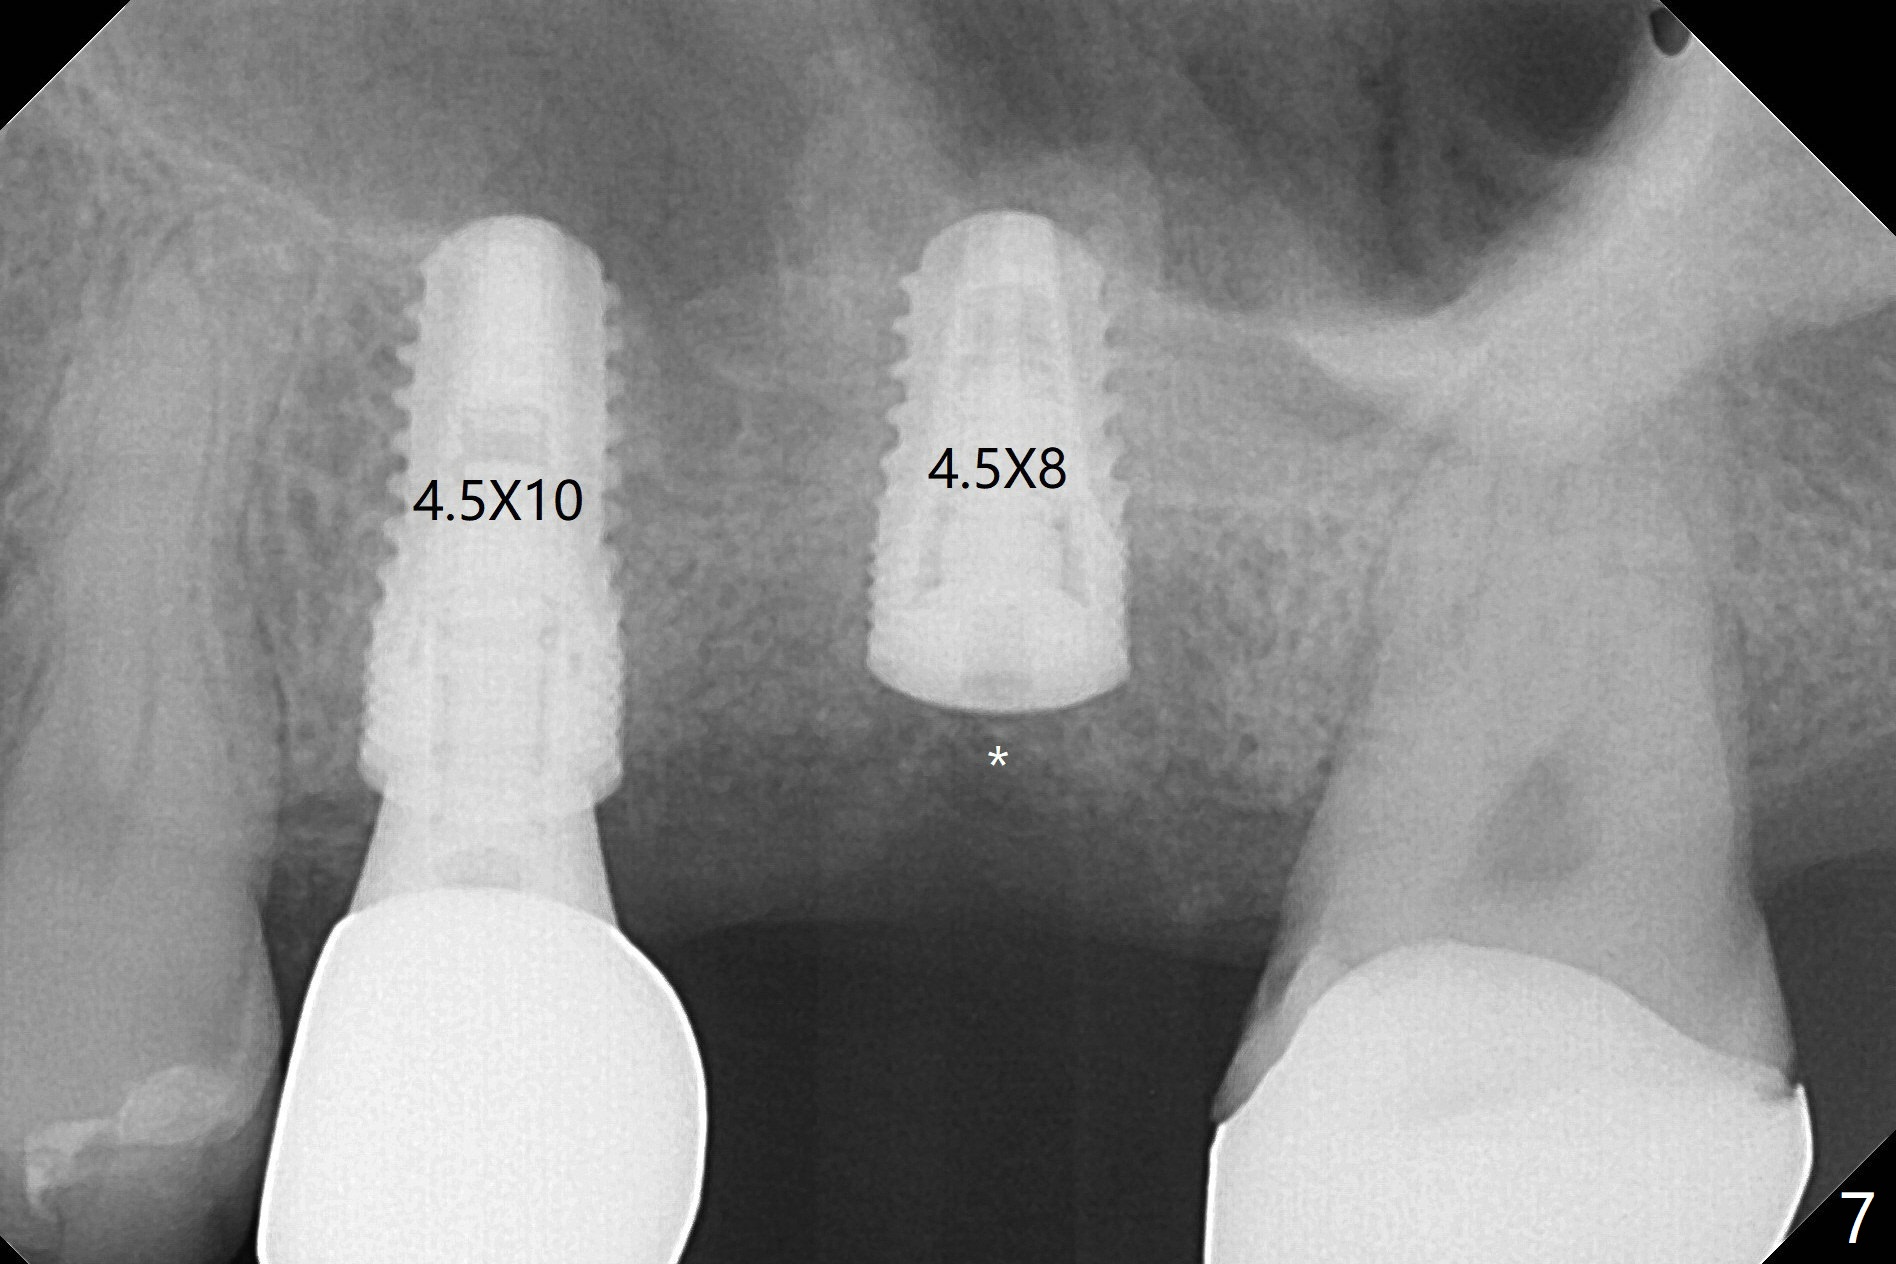

60岁男,左上6(牙根折裂严重骨质吸收)位点保存后6个月,回来植牙。术前CT显示骨质密度低,宽度足够,角化龈也宽,前后牙齿都有牙冠,制作导板麻烦,所以采纳徒手种植。使用4毫米活检打孔刀(Biopsy Punch)进入,简化手术,但是又怕开口不正,不敢用大号植体,术后CT发现钻洞偏颊侧。针对骨质密度低,使用1.2毫米钻头后(约8毫米),使用旋转式骨扩张器直至2.4/3.7毫米(图一(红虚线:原来骨质缺损)逐渐增加深度至11毫米),备洞几乎没有失去骨质,钻洞周围骨质密度谅必增高),取出最后一个扩大器后发现上颌窦底板破裂,放置粘性骨粉,使用4毫米报废植体做上颌窦提升,重复一次(图二,三),稳定性尚可。再次放置骨粉和PRF膜,使用正式植体提升(4.5x8毫米),临床上很难判断是否植体植入牙槽嵴之下(可能骨质疏松),只好拍摄CT(图四,五),好像正好牙槽嵴下,不过又植入骨粉一些(图七:*)。植体扭力~15Ncm,保险起见,放置愈合帽,表面放置少许骨粉以及打孔留下的牙龈(图六:G,之前一直泡在PRF上清液里),牙周胶水固定游离牙龈以及牙周敷料保护。术后6小时没有鼻出血。所以骨质缺损严重,植骨后,虽然缺损外形得到恢复,但是骨头质量,固定植体能力还不够。植牙时,需要适当改变手段,例如使用骨凿,提高骨质密度,而不是单纯使用钻头。术后病人恢复正常,没有疼痛,六天复诊,牙周敷料已经脱落,打孔的牙龈附着颊侧,部分骨粉暴露,但是看样子挺稳定,好像游离牙龈必须缝合。使用树脂敷料牢靠些。术后五周,伤口基本愈合,一处未愈合,与下面骨粉相通,用牙周探针稍微搅动,出血(图九)。擦干血迹,伤口还不错(图十)。术后2个月伤口好像正常愈合(图十一)。术后4.5个月根尖片显示6种植比5深,往后螺纹暴露可能性减少(图十二)。